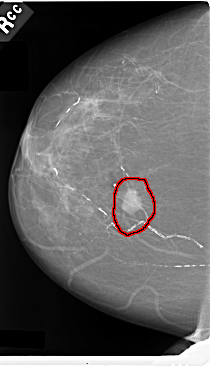

C_0031_1.RIGHT_CC

FILE: C_0031_1.RIGHT_CC.OVERLAY

TOTAL_ABNORMALITIES 1

ABNORMALITY 1

LESION_TYPE MASS SHAPE IRREGULAR MARGINS SPICULATED

ASSESSMENT 5

SUBTLETY 5

PATHOLOGY MALIGNANT

TOTAL_OUTLINES 1

BOUNDARY